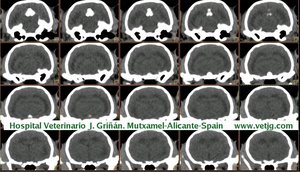

imágenes de TC en el gato | |||||||||||

Tomografía computarizada helicoidal |